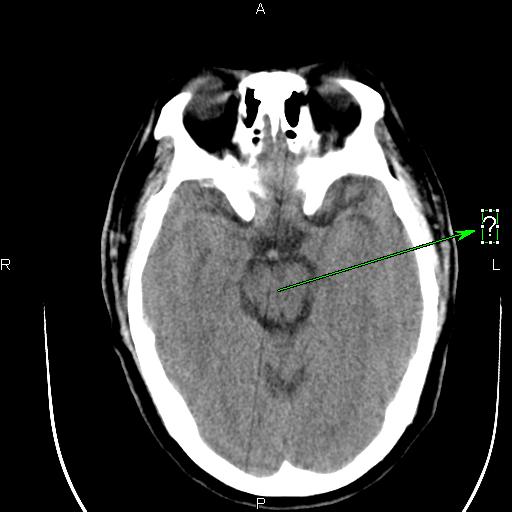

这种伪影是怎样造成的?怎样解决呢?

应该是某个通道跳起引起的直线伪影。你可以在过滤成像里检查一下,应该可以看到一跟亮线,找到是某个通道,然后屏蔽就可以了。另外一种方法就是,在ps里,不放线,不旋转,之间看所有的通道值,有没有跳起的?在ps里,放线,不旋转,这样可以看得更加清晰!你可以找到跳起的通道,或你也可以找到相应位置的das板,然后把有问题的das板换到边上,这样也可以解决问题。应该是检测器中间部位的某个das板或是通道引起的伪影